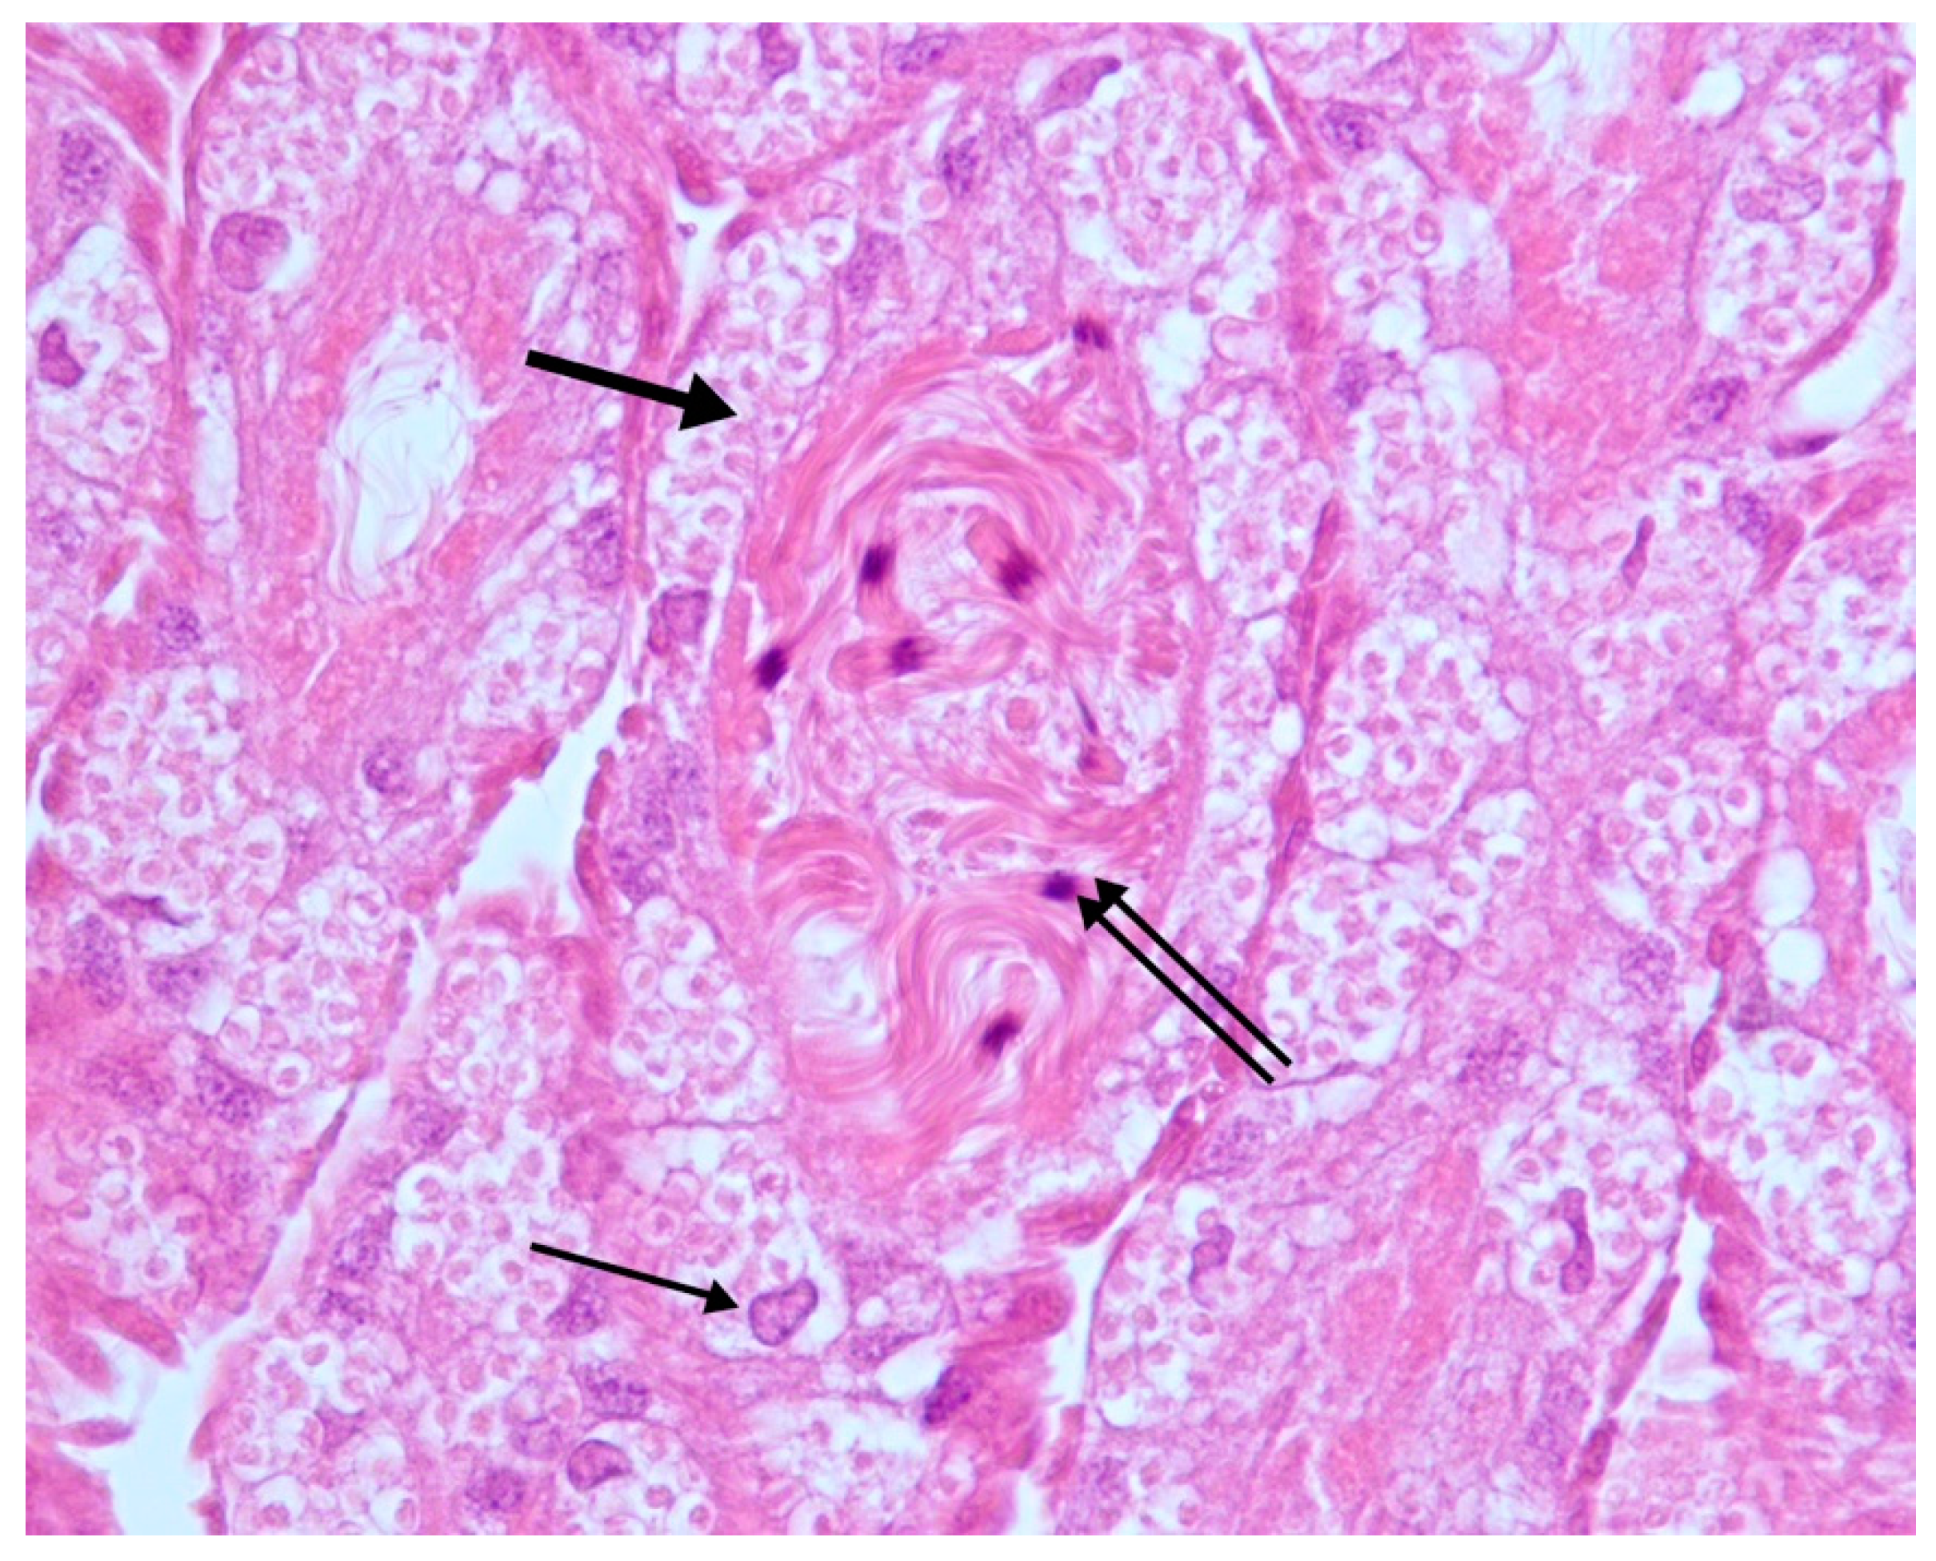

Histopathological Findings in Testes from Apparently Healthy Drones of Apis mellifera ligustica

3. Results